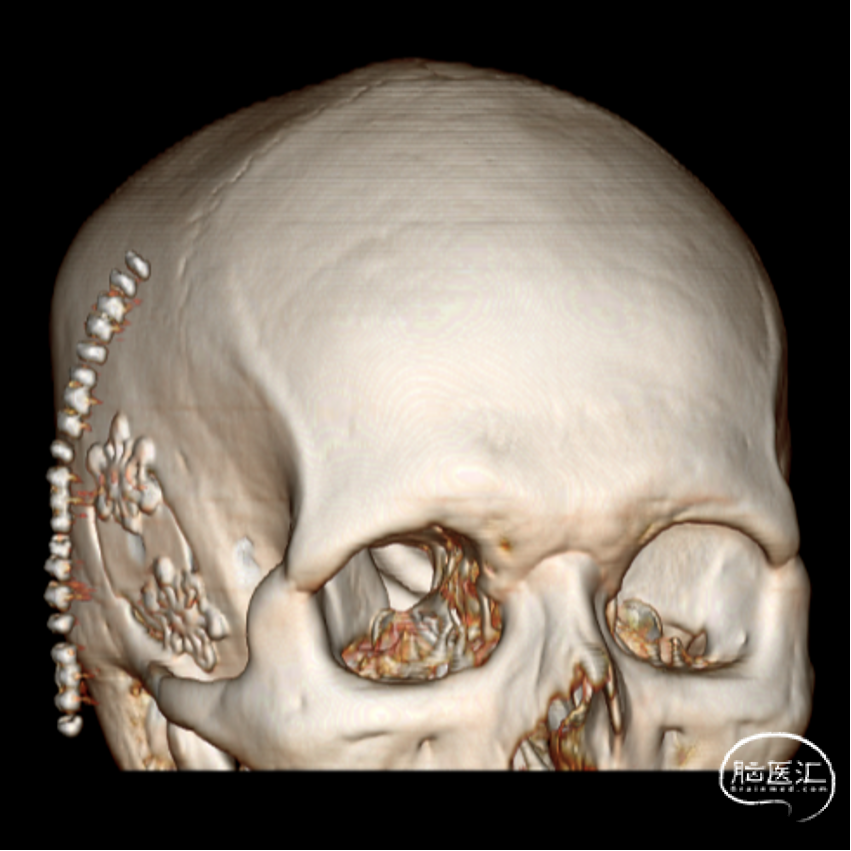

外院CT示:右侧颅底占位性病变,临近骨质部分吸收。

王杰教授团队:颞下锁孔入路颅底胆脂瘤切除术